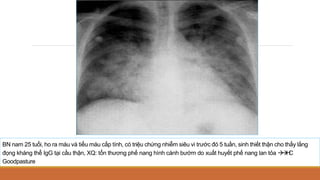

BN nam 25 tuổi, ho ra máu và tiểu máu cấp tính, có triệu chứng nhiễm siêu vi trước đó 5 tuần, sinh thiết thận cho thấy lắng

đọng kháng thể IgG tại cầu thận, XQ: tổn thương phế nang hình cánh bướm do xuất huyết phế nang lan tỏa 



H

C

Goodpasture

5. HÌNH CÁNH BƯỚM (CÁNH DƠI)

5. HÌNH CÁNH BƯỚM

Nguyên nhân:

◦ Phù phổi cấp (đặc biệt OAP do tim)

◦ Viêm phổi

◦ Tổn thương phổi do hít khí độc, chất lỏng

◦ Bệnh lắng đọng protein phế nang

◦ Xuất huyết phế nang

◦ Lymphoma, leukaemia

◦ Ung thư tiểu phế quản phế nang (UTTPQ-PN)

PHÙ PHỔI CẤP